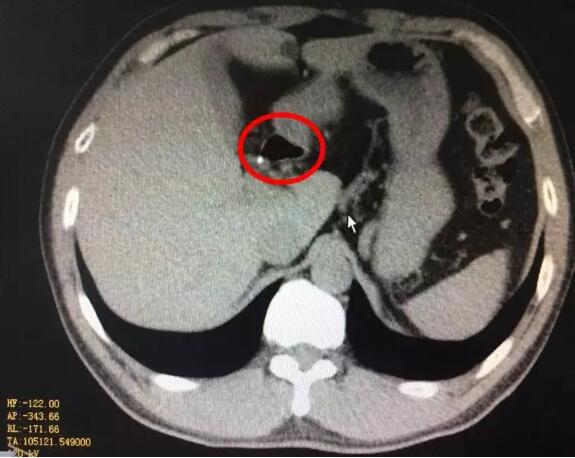

很快,化验结果出来了,血淀粉酶2714U/L,腹部CT提示胰腺水肿,急性胰腺炎诊断明确。立即给予胃肠减压、制酸、抑酶等综合治疗。第三天复查CT提示坏死性胰腺炎,只有少量胰腺组织残留,并出现肺功能、肝功能受损和腹腔积液等并发症。